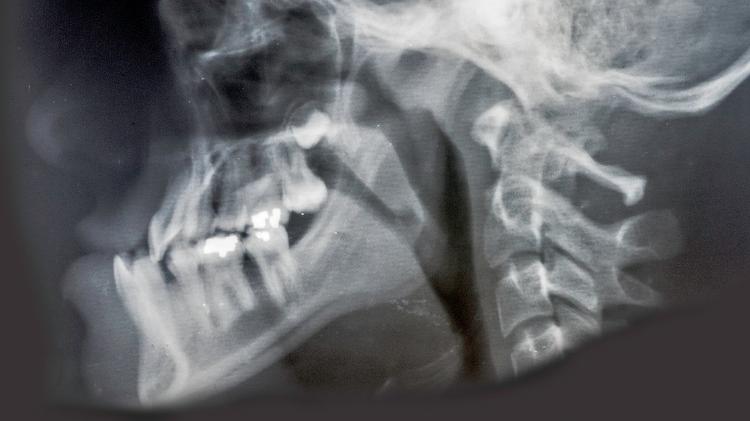

Essa condição, chamada prognatismo, ocorre devido ao excesso de crescimento da mandíbula (osso inferior móvel) ou à falta de crescimento da maxila (a parte superior), causando um posicionamento inadequado entre a arcada dentária superior e inferior.

A desarmonia estética pode ser observada desde a infância, mas se agrava ao longo dos anos. Gera desde problemas de mastigação, deglutição e fala a respiratórios e dentários, como perdas de dentes, maus posicionamento e encaixe de mordida e desgastes precoces, além de tensão e disfunção na articulação temporomandibular (DTM), dores na coluna, má qualidade do sono, gerando ronco ou apneia, desordens psicológicas e baixa autoestima pela aparência.

Na visão de frente, os segmentos da face podem ser divididos horizontalmente em: terço superior (região frontal), terço médio (região dos maxilares) e terço inferior (região da mandíbula). A relação ideal entre os terços é de 1:1:1, ou seja, os três segmentos devem apresentar a mesma altura.

"Na visão da face em perfil, a harmonia se encontra na adequada projeção de cada um desses segmentos, sendo considerado normal a face que apresenta praticamente as mesmas projeções ósseas dos terços superior, médio e inferior", diz Martins.

Agora, o queixo posicionado mais ao fundo, destacando a maxila (parte superior frontal), o nome dado é retrognatismo mandibular. Essa condição pode ser congênita e hereditária, sindrômica (relacionada, por exemplo, à síndrome de Pierre Robin) ou ainda estar relacionada a algum fator que impeça o crescimento normal da mandíbula durante seu desenvolvimento, tais como: trauma (principalmente fratura do côndilo mandibular, a eminência arredondada na extremidade do osso mandibular) e respiração oral na criança, embora não haja consenso médico com relação a esta última.